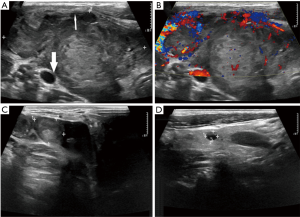

The dominant sonographic findings of PTL were large (average 4.8±1.7 cm, range 1.6–8.7 cm), solid (100%), ill-defined (81.5%) mass with echogenic strands (92.6%), posterior echo enhancement (85.2%) and without calcification (100%) (Table 2), while the dominant sonographic findings of ATC were large (average 5.8±2.1 cm, range 2.5–11.0 cm), solid (100%), ill-defined (100%) mass with macrocalcification or microcalcification (80%) (Table 2). PTL cases presented with diffuse type (25.9%) (Figure 1), nodular type (48.2%) (Figure 2) and mixed type (25.9%) (Figure 3). All ATC cases presented with nodular type (100%) (Figures 4,5). There is no significant difference in thyroid size, nodular size, margin, shape, echo texture, cystic change and vascularity on sonography between ATC and PTL groups (Table 2).

With regard to tumor-spreading patterns, in 15 patients with ATC, 13 patients had extra-thyroid extension into the surrounding soft tissue (Figure 4A), 1 patients invaded trachea, and 2 patients invaded jugular vein. In 27 patients with PTL, 14 patients had extra-thyroid extension into the surrounding soft tissue (Figures 2A,B,3B), 1 patients invaded trachea (Figure 1C).

In our ATC group, 52.9% (9/17) of ATC cases showed intratumoral calcification, including microcalcification, macrocalcification and mixed calcification. In previous studies by Takashima et al. (30) and Ishikawa et al. (31), the authors demonstrated calcification was one of the dominant computed tomographic findings in ATC. Lee et al. (32) also reported that 44.4% of anaplastic carcinomas showed nodular calcification. In contrast, none of the PTL cases showed intratumoral calcification.

The coexistence of well-differentiated and ATCs has been well demonstrated in several studies (43-46), however, whether it arises from a preexisting well-differentiated thyroid carcinoma (e.g., papillary thyroid carcinoma, PTC) is not clear. That might explain why ATC present with some characteristics of PTC, such as microcalcifications. In our study, 4/15 patient had zones of PTC (n=3) or adenocarcinoma (n=1) in the ATC lesion, and 1 patient had PTC in the contralateral lobe of thyroid. One patient with ATC had a surgery of local excision of one side lobe because of PTC 1 year ago.